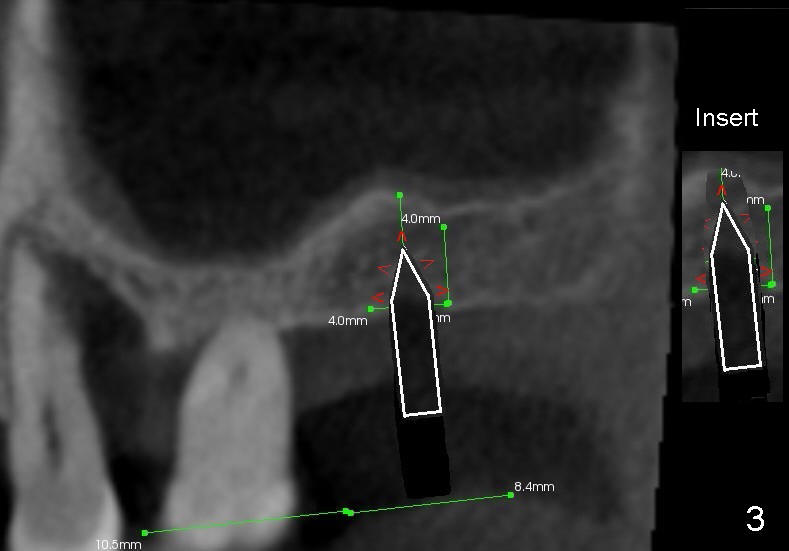

Fig.1 is a sagittal section of the posterior maxilla. A 2 mm (in diameter) round straight osteotome (white box) is going to initiate osteotomy and sinus lift. When the osteotome penetrates the bone initially, the latter is going to be condensed and pushed laterally (mesiodistally) and apically (Fig.2,3 arrows).